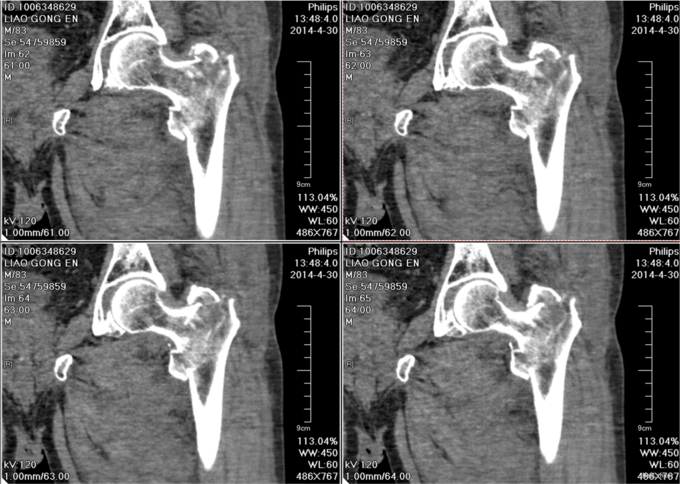

患者2014-04-27日上午9时摔倒后左髋部疼痛肿胀、活动受限,不能站立行走,急来中国医科大学附属盛京医院急诊科,急诊予以行辅助检查,左下肢DR提示:左股骨粗隆间骨折,现患者为求进一步诊治,以“左股骨粗隆间骨折”为诊断收入我科。患者自受伤以来一般状态可,无发热,无头晕、呕吐,无胸闷、心悸呼吸困难,无腹痛、腹泻,饮食可,睡眠可,二便正常。

左髋部未见明显肿胀及瘀斑,活动度减低,活动因疼痛受限,左髋部压痛阳性,叩击痛阳性,左下肢缩短畸形,缩短1cm,外旋80°。左膝及左踝关节活动无明显异常。双侧足背动脉搏动有力,肢体末梢血运良好,皮温正常。远端足趾感觉运动正常,

入院后完善检查,查无手术禁忌症后行左股骨粗隆间骨折闭合复位内固定术。患者术后第二天下地行走,术后3天自动退院。